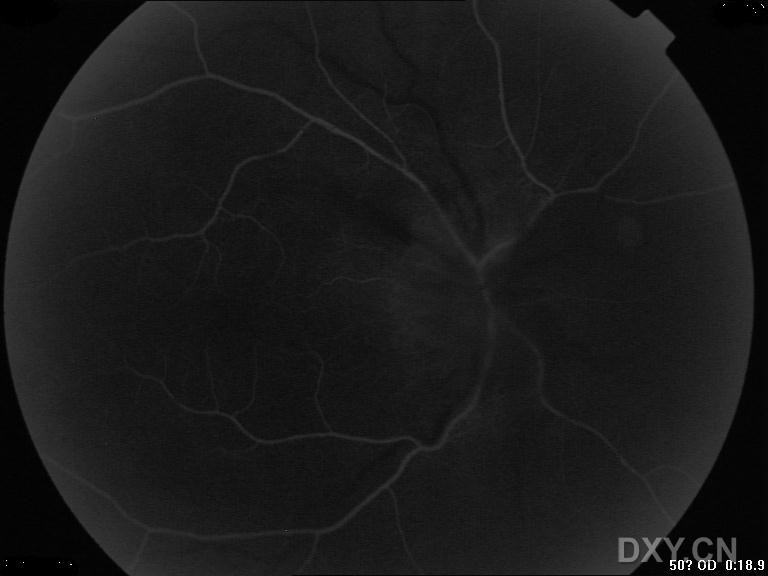

考虑前部缺血,但循环时间尚可.

MR已排除颅内占位 后期渗漏

本例病人考虑为缺血性视乳头病变 1、视乳头主要由睫状后短动脉供血,凡是可以产生睫状动脉狭窄、闭塞或使视乳头灌注压降低的病变,均可造成视乳头缺血。其局部亲和因素是小视乳头,全身亲和因素是糖尿病、高血压、动脉硬化。(本例病人有高血压病史) 2、本病多发生于40-70岁,多为双眼,但一般不同时发病,两眼可间隔数周至数年。 3、视力突然减退,一般轻度或中度下降,发病前多有一过性视糊。RAPD(+) 4、眼底:视乳头色淡、界糊、水肿,多见视乳头及其附近网膜有线状或火焰状出血,网膜动脉较细,静脉轻度扩张。 最好能有病人的视野、FFA资料 视野多表现为与生理盲点相连的象限性缺损,常在下方。 治疗方案:降血压、扩张微循环,可同时全身应用糖皮质激素,以缓解微循环障碍所致水肿、渗出,大剂量使用,以保护第二眼免于发作(强的松片1.0-1.2mg/kg.qm)